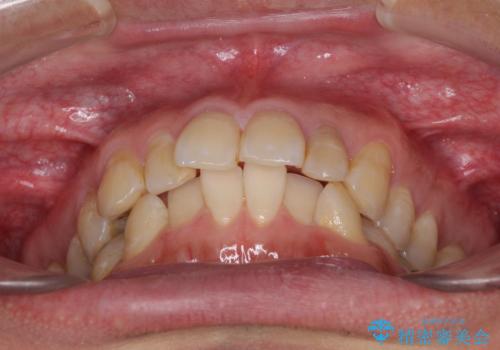

前歯のデコボコと下顎の八重歯 インビザラインによる矯正治療

- 前歯のデコボコや八重歯を気にして来院された患者様です。

インビザラインを用いて、歯列を整えることとしました。

下顎前歯は後戻りを起こしやすいため、舌側を細いワイヤーで固定し、マウスピース型リテーナーで保定を行うこととしました。